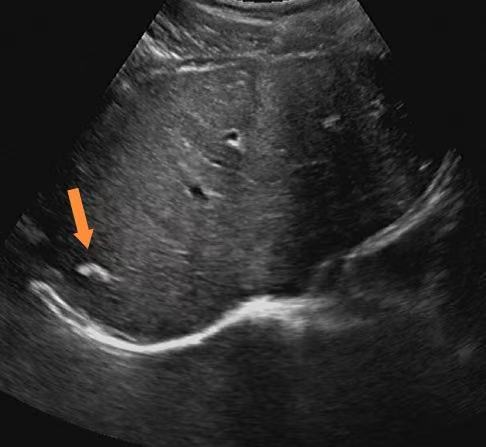

肝内钙化灶,简单说就是肝脏局部组织里的钙盐沉积。你可以把它想象成身体为了修复某个微小的肝脏损伤,而留下的一个"小补丁"。在B超或CT影像上,这些钙盐沉积会呈现为一个或多个白色的亮点。